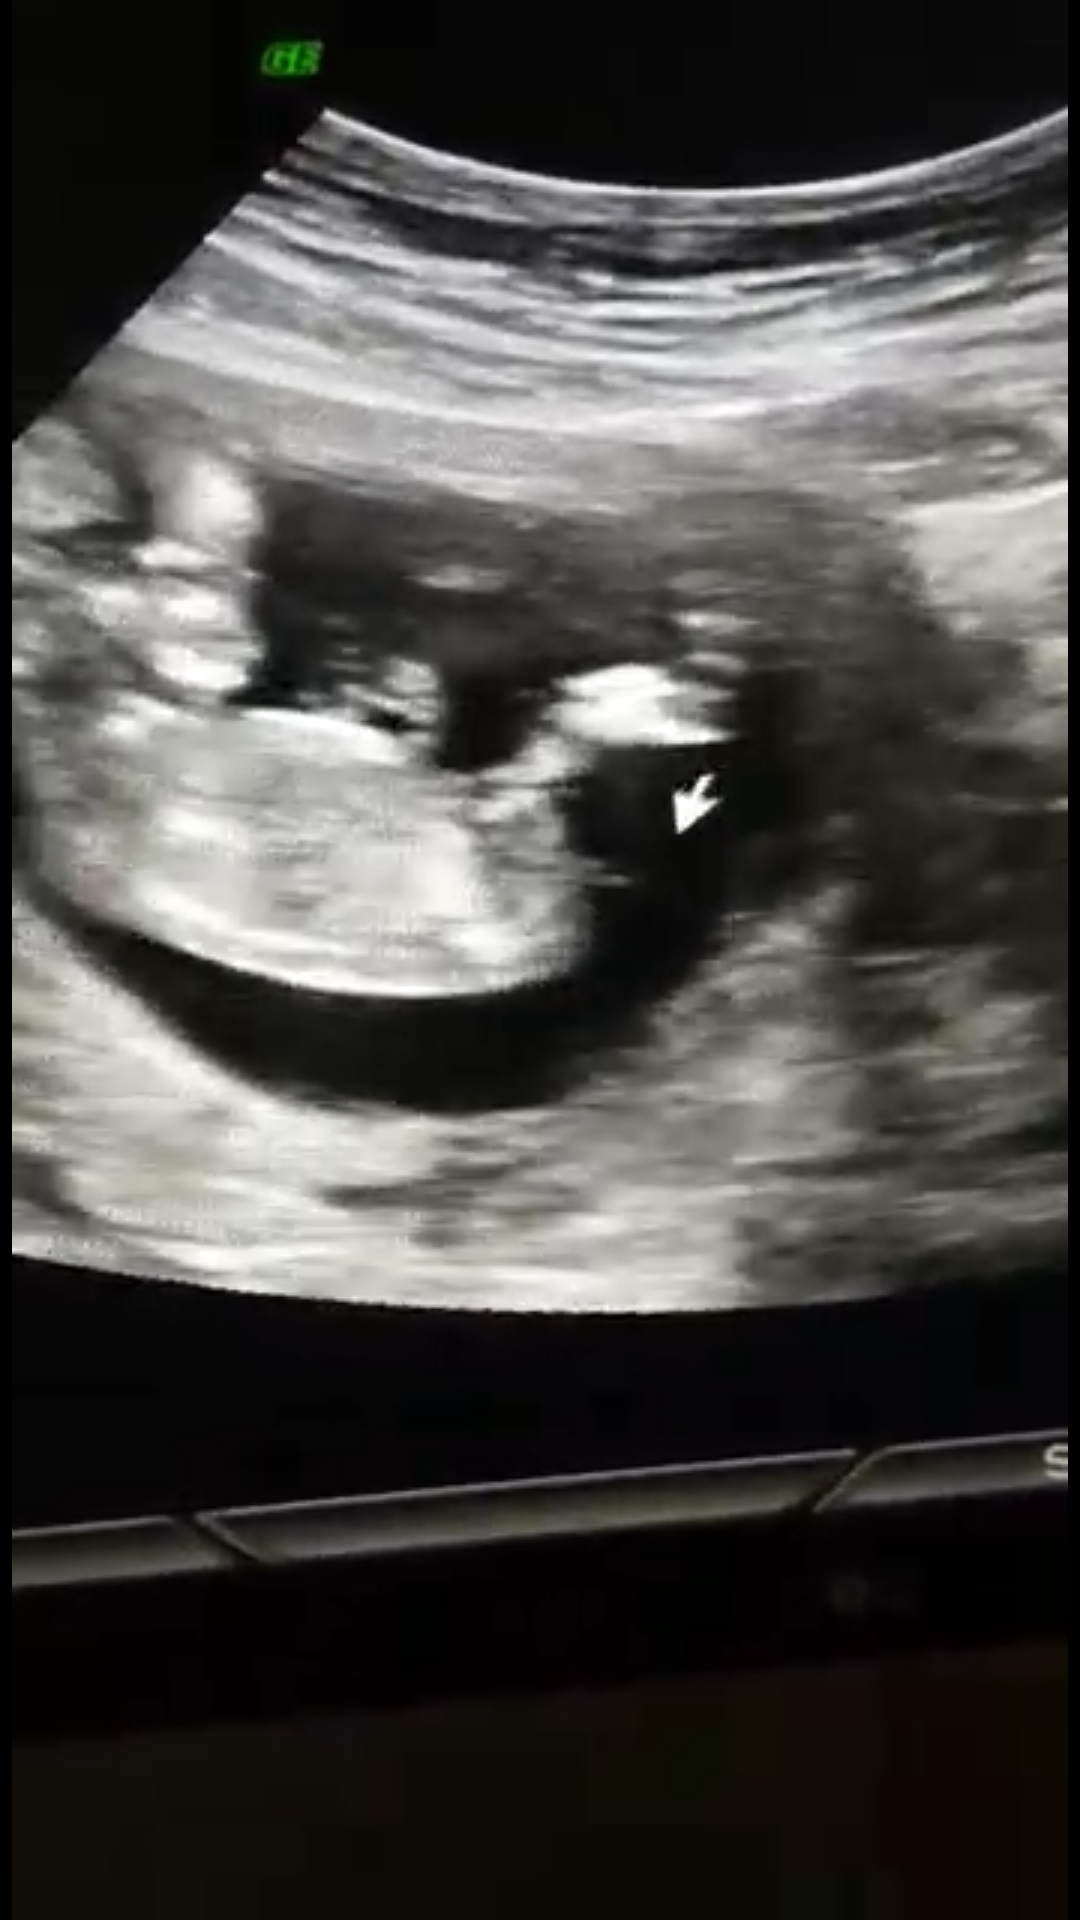

Bizlere ulaşan sevgili Ezgi kardeşimizin gönderdiği resmi ekliyorum meleklerim. Sizler de info@meleklermekani.com adresine ultrason resimlerinizi gönderebilirsiniz. Resimler net olsa iyi olur. Sevgili Ezgi tam istediğimiz netlikte değil hayatım ama bebeğinin Erkek olacağını düşünüyorum. Yüzde yüz budur diyebilseydim keşke ama çıkıntıyı gördüğümü düşünüyorum. Hayırlı olsun hayatım.

nub cinsiyet tahmini ezgi dolanbay.jpg

Daha başka resim var ise özellikle çıkıntının olduğu bölümü atabilirsen daha net sonuç verebiliriz.

Sevgili Ezgi, evet mail ile ulaşmışsın bizlere ama soru cevapları bu konu üzerinden devam ettirelim ki sizin durumunuzda olup bebeğinin cinsiyetini merak eden anne adaylarına da ışık olsun. Dediğiniz gibi ben o çıkıntıyı acaba kordon mu diye düşündüm ama iyice inceleyip büyütünce çıkıntıya göre şimdi erkek diyebiliyorum. Hayırlısı bakalım 🙂